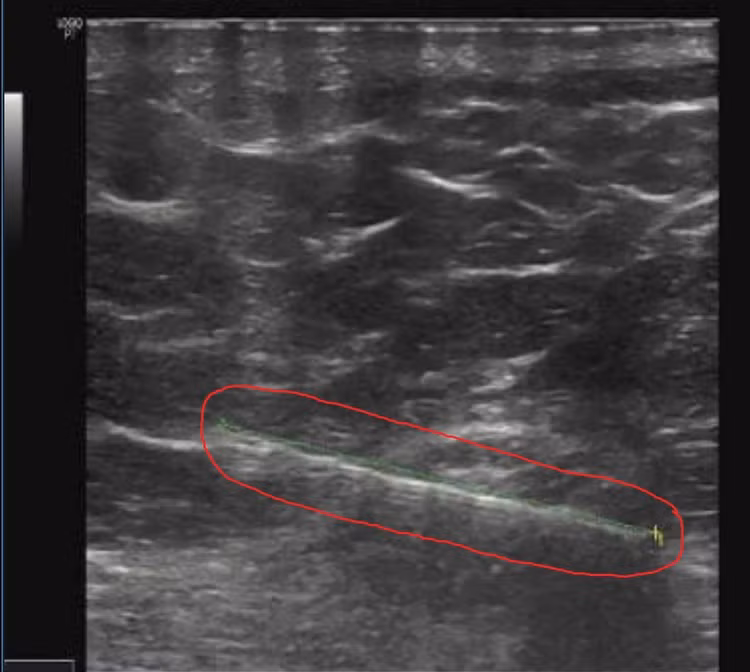

BSCKII Kiều Quốc Hiền chia sẻ, rất may cho người bệnh này, hệ thống phòng mổ của Bệnh viện E có hệ thống máy siêu âm 3D thường được sử dụng trong định vị sỏi khi thực hiện kỹ thuật tán sỏi qua da hoặc xác định vị trí đám rối thần kinh trong gây tê đám rối hoặc xác định ven trung ương khi phải can thiệp đặt ven trung tâm…

Nay, dưới sự hỗ trợ của hệ thống máy siêu âm 3D hiện đại này, BSCKII Kiều Quốc Hiền cùng các cộng sự đã dễ dàng lấy dị vật sắc nhọn bằng kim loại cho người bệnh một cách nhanh chóng. Chỉ sau 5 phút, gây tê, các bác sĩ đã lấy ra một chiếc kim khâu dài 5cm, chưa hoen rỉ nằm sâu trong cơ mông của người bệnh.